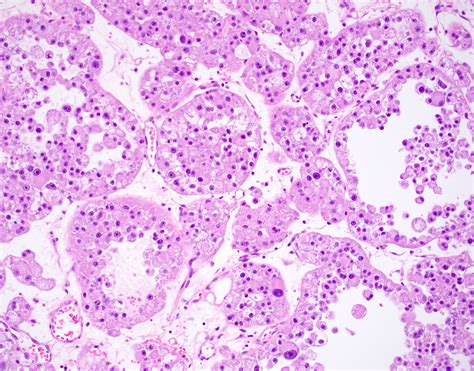

ASPS is a type of soft tissue sarcoma that originates from the mesenchymal cells, which are responsible for the formation of connective tissues. The disease is named for its distinctive alveolar pattern under the microscope, which resembles the structure of lung alveoli. This pattern is a key diagnostic feature that helps differentiate ASPS from other types of sarcomas.

Histopathological examination reveals the characteristic alveolar pattern of ASPS, which is essential for a definitive diagnosis. Additionally, immunohistochemical staining and molecular genetic testing can provide further confirmation.